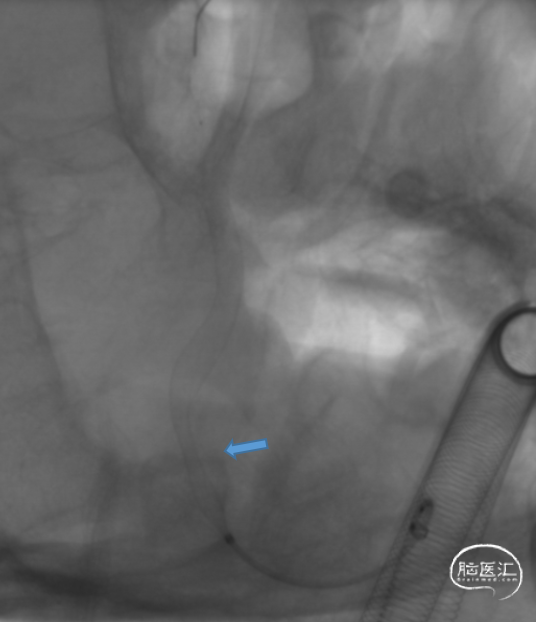

J-Tube™打开过程-整体显影性能良好。

J-Tube™血流导向密网支架打开过程。

动脉瘤近端血管狭窄

回收密网支架重新释放,狭窄依然存在。